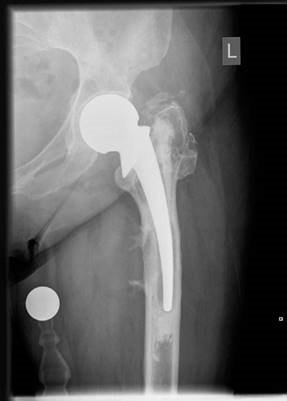

EXAMINER: This is a radiograph of a 77-year-old woman who sustained a displaced intracapsular fractured neck of femur 3 years earlier managed with a hemiarthroplasty of the hip (see Figure 2.1). She was admitted onto the orthopaedic ward last night because of increasing left hip pain and difficulty mobilizing.

CANDIDATE: This is an anteroposterior (AP) radiograph of the pelvis taken on the 11/5/11 demonstrating a cemented Thompsonโs hemiarthroplasty of the left hip. The neck cut is straight down on to the lesser trochanter. The prosthesis seems to have sunk below the lesser trochanter and there are radiolucencies in Gruen zones 1, 4, 5 and 7. There appears to be a faint rim of calcification in the soft tissues, adjacent to the lateral cortex of the femur. The femoral head size would seem to match the acetabulum so it is not under or oversized and the femoral stem orientation appears neutral, neither excessively anteverted

nor retroverted. I would like to see immediate postoperative radiographs to confirm whether there has been a change in stem position from the time of the original surgery and would also like to see an up-to-date lateral radiograph of the hip.

Figure 2.1 Anteroposterior (AP) radiograph of loose left cemented Thompsonโs hemiarthroplasty hip.